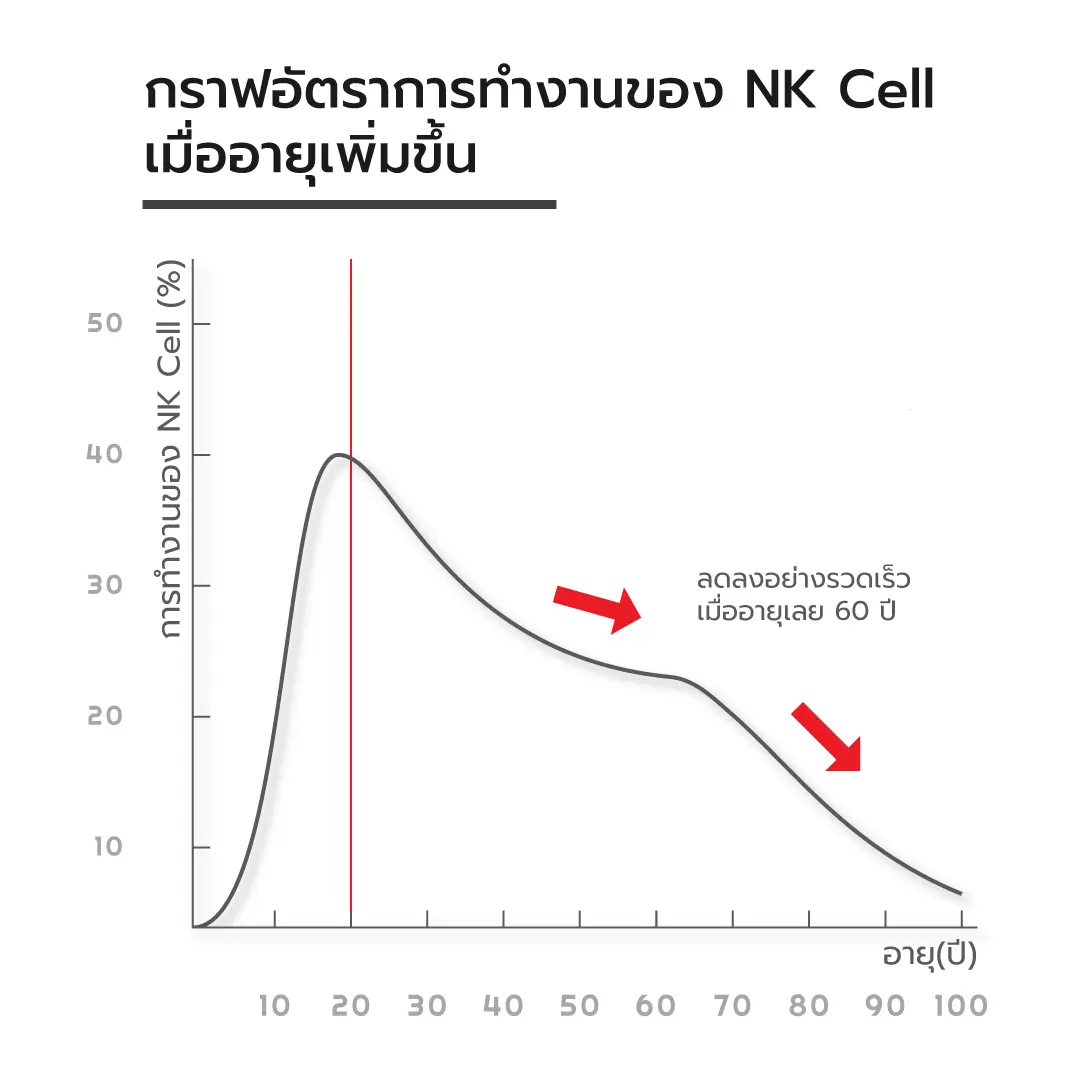

อย่างไรก็ตามในสภาวะปกติ เม็ดเลือดขาว NK Cell พบได้ค่อนข้างน้อยในกระแสเลือด โดยมีเพียง 5 % ของจำนวนเม็ดเลือดขาวชนิด lymphocyte ทั้งหมด รวมทั้งจากการศึกษาพบว่า NK Cell จะลดลงเมื่ออายุเพิ่มขึ้น ซึ่งสัมพันธ์กับอุบัติการณ์มะเร็งที่เพิ่มขึ้นตามอายุด้วย